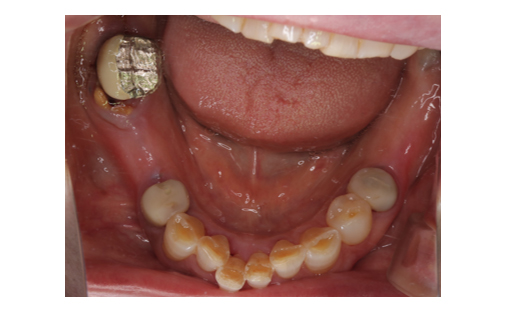

骨造成とインプラント

下顎の骨量が乏しいため骨造成をし、その後インプラント治療を行いました。

かみ合わせも良好でしっかりと機能しています。